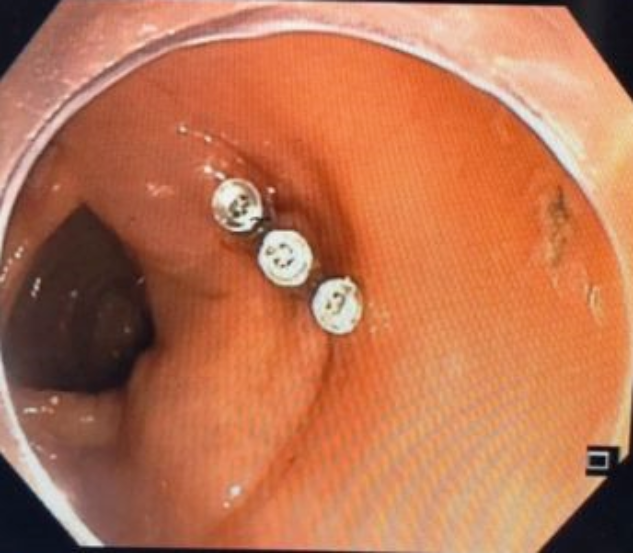

胃肠科手术室内消化专家宋国彬与护士姜士秀的紧密配合按照计划顺利实施手术,在粘膜下注射生理盐水2ml,粘膜切开刀环周切开,剥离后暴露瘤体,完整剥离后置3枚和谐夹缝合创面,历时2个小时的手术,术程顺利,无出血及穿孔。

术中